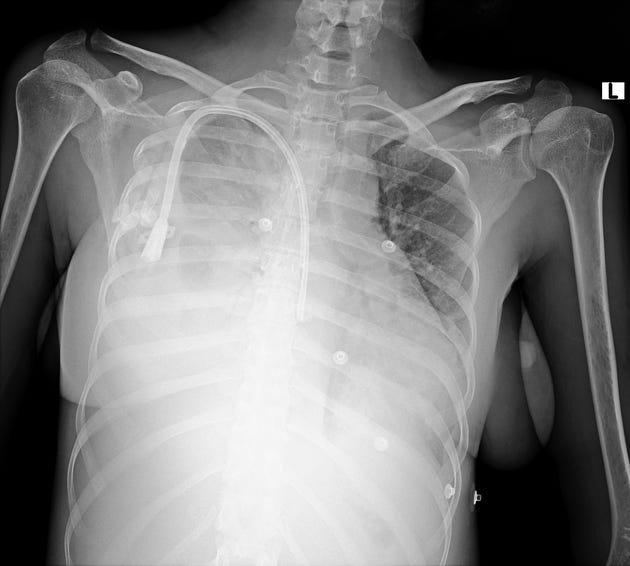

A chest film after the procedure two days ago was unremarkable. A new chest radiograph is obtained.

The patient has a new large pleural effusion with borderline hemodynamic instability and worsening hypoxemia.

With a significant drop in hemoglobin and a new large right-sided pleural effusion ipsilateral to a recently placed tunneled dialysis catheter in the subclavian vein, iatrogenic hemothorax is a likely diagnosis.